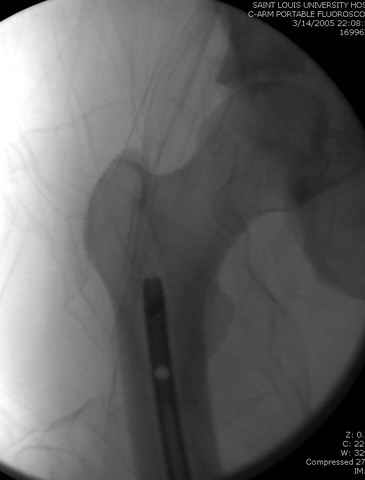

03.14.2005

больному 42, автоавария, политравма, открытая черепномозговая травма, безсознании, открытый перелом бедра, размозжение мягких тканей, дефект кожи на передней поверхности бедра около 13 см2 от ожога, компартмент синдром.

По поводу открытого перелома больной ургентно взят на ретроградное интрамедулярное штифтование, после рутинного дебрайдмента и фасциотомии на бедре и на голени.

интраоперационные